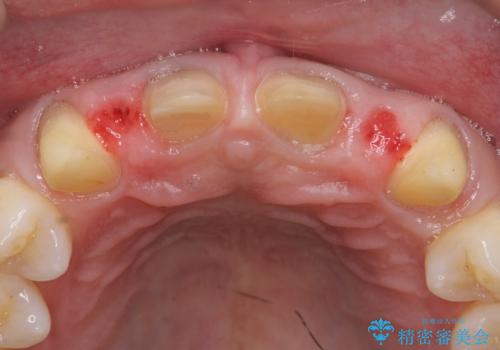

- 前歯部のすきっぱと歯並びが気になるので診て欲しいといらっしゃった方の症例です。

全顎矯正は御希望されなかったため、上顎前歯部のみの部分矯正とオールセラミッククラウンによる補綴を行いました。

- オールセラミッククラウン…¥100,000×6、仮歯…¥10,000×6、部分矯正…¥200,000費用は治療当時の料金となります

今回用いたオールセラミッククラウンはジルコニアフレームという白い素材の上にセラミックを盛っているため、審美性が非常に高いのが特徴です。

また、ジルコニアは人工ダイヤモンドの材料にも使われているほど高い強度を持っており、そのためオールセラミッククラウンは審美性だけでなく、奥歯やブリッジの補綴も可能とするクラウンです。